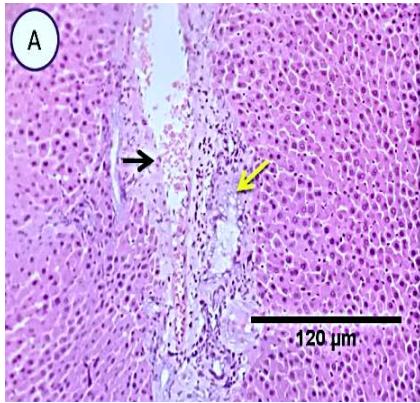

Liver: Examined sections from liver of this group denoted moderate portal biliary proliferation, congestion of portal blood vessels, round cell infiltration, multifocal interstitial lymphocytic and macrophages aggregations replacing previous necrotic patches beside degenerative changes in a few hepatocytes.(Fig.7).

Fig. 5: Photo-micrograph from liver, group (3), showing, portal biliary proliferation (yellow arrow), congestions of portal blood vessels (black arrow) and round cell infiltration and interstitial lymphocytic and macro-phages aggregations replacing previous necrotic patches (orange arrow). Scale bars 120, 40, 40 um.